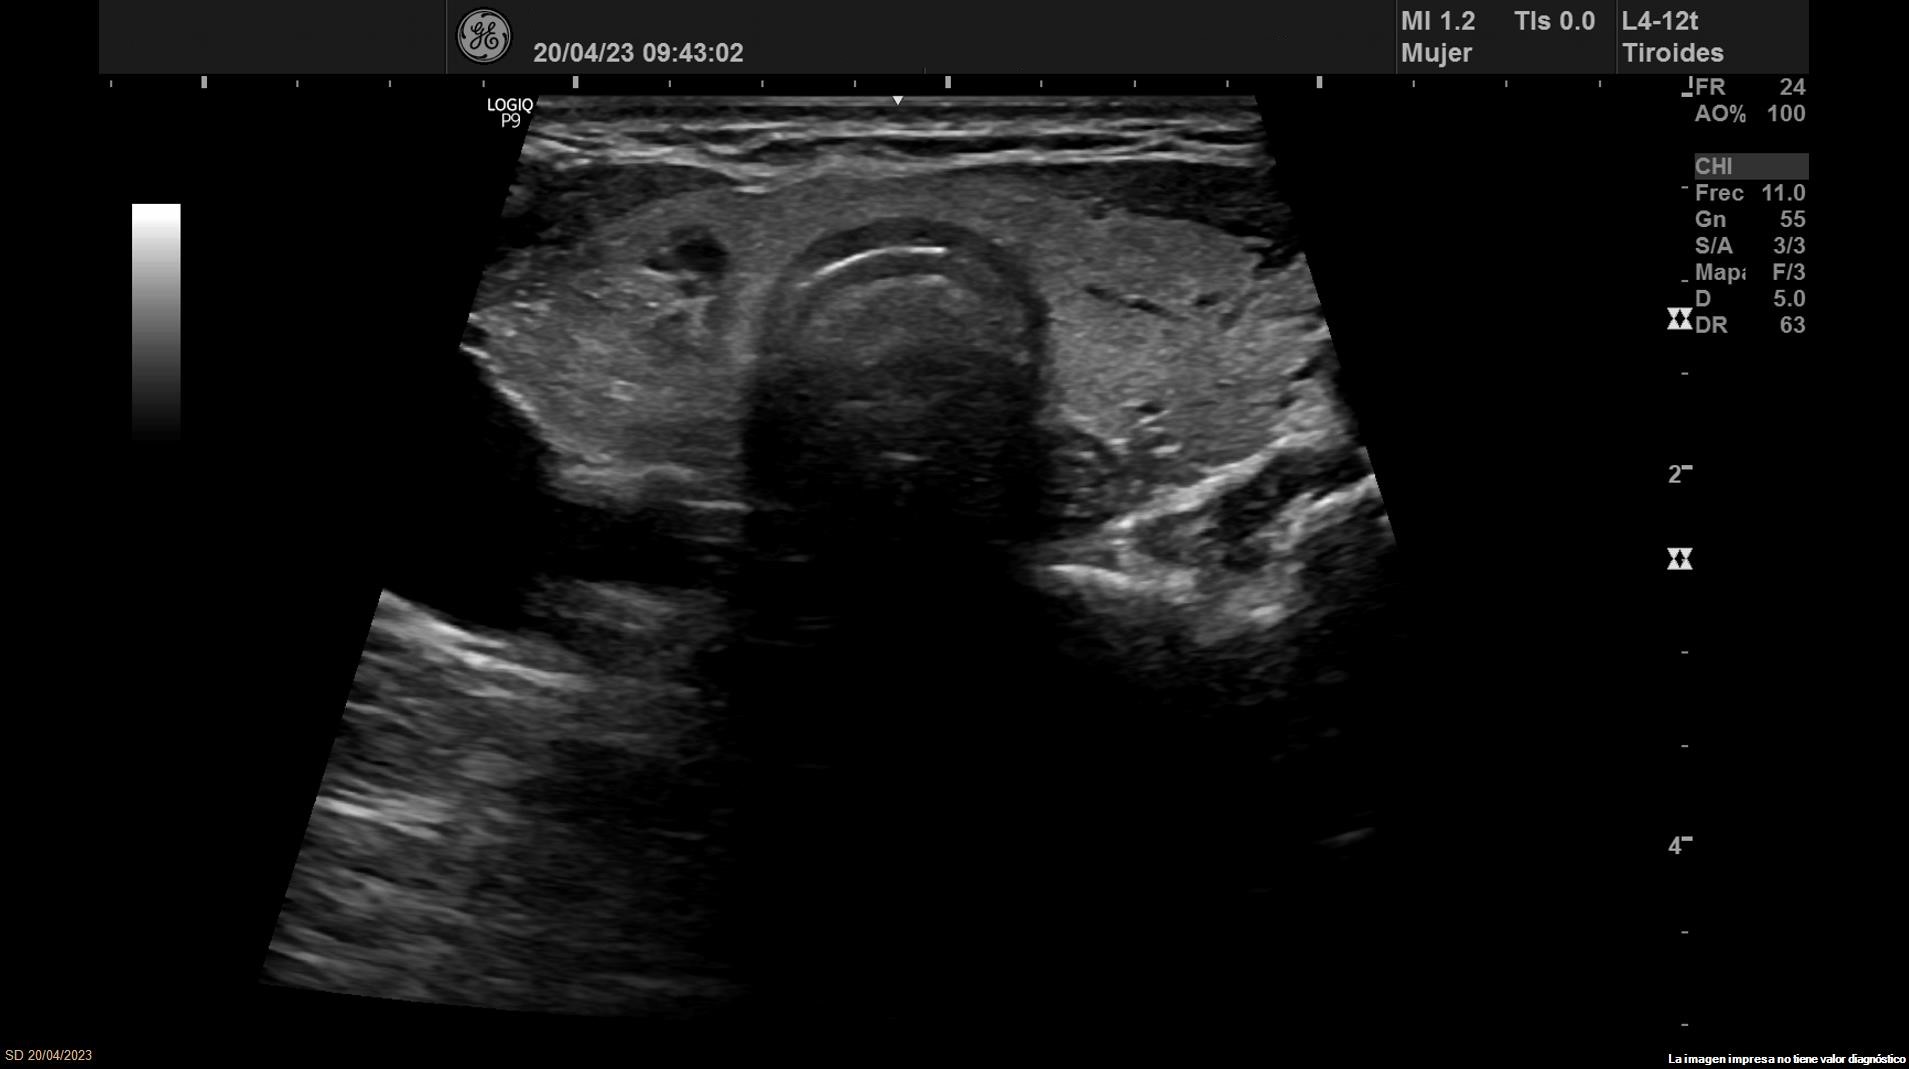

• Lóbulo tiroideo izquierdo: tamaño normal. En la mitad inferior se objetiva un nódulo de 11 x 14 x 20 mm (Vol 1,52 ml), bien definido, sólido e iso/hiperecoico, con halo fino hipoecoico, sin calcio y con vascularización de predominio periférico (ATA: baja sospecha).

• Lóbulo tiroideo derecho: tamaño normal. En tercio inferior nódulo único espongiforme con área quística inferior que mide 15 mm de diámetro mayor longitudinal (ATA: baja sospecha).